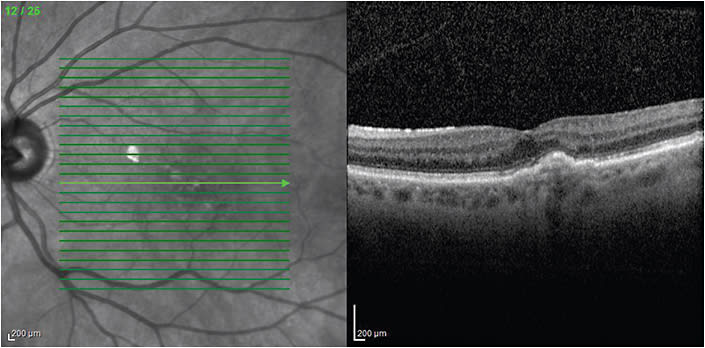

Dr. Haupert uses the treat-and-extend strategy. He says the interval between visits can often be safely extended for many patients (Figures 1-3). In fact, he reports a substantial number of his patients respond well to receiving treatment every three months.

Figure 1. Baseline study shows subfoveal hyperreflectivity, consistent with subfoveal choroidal neovascularization, subfoveal fluid and mild foveal thickening. Visual acuity was 20/70. Bevacizumab (Avastin, Genentech) treatment began that day.

Figure 2. Three months after the baseline visits, following three monthly bevacizumab injections. Mild subfoveal elevation of the retinal pigment epithelium with resolution of all macular fluid. Visual acuity improved to 20/40.

Figure 3. Eighteen months after the baseline exam, following nine bevacizumab injections using a treat-and-extend strategy. The prior three injections were administered at three-month intervals. Shows no significant change from the study performed at the three-month point, still without any macular fluid. Visual acuity improved to 20/20.

“I typically administer three monthly injections, after which I obtain spectral-domain optical coherence tomography (SD-OCT) to assess for residual macular fluid,” Dr. Haupert explains. “If all intraretinal and subretinal fluid has resolved, I administer an additional injection and increase the interval between injections by two weeks at a time, administering injections and checking SD-OCT at each subsequent visit. As long as there is no recurrence of fluid, I continue to extend the interval between injections. While the majority of our patients require treatment more frequently than every three months, some do quite well with intervals of three months or even longer.”